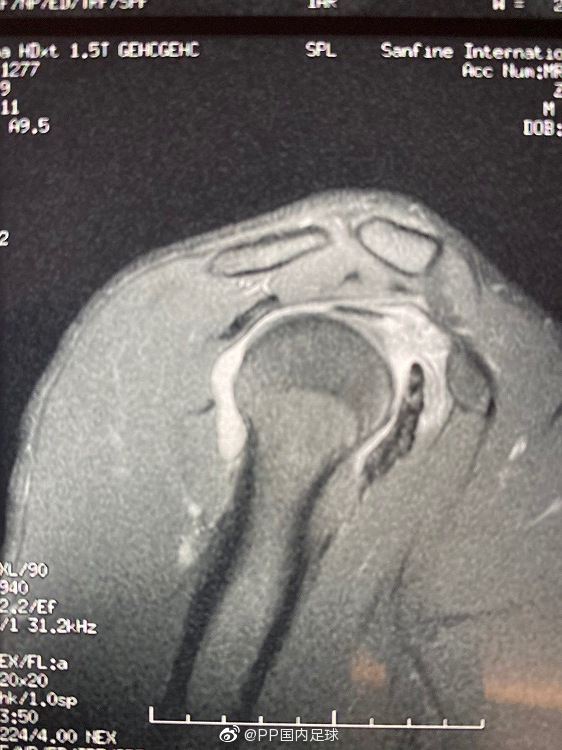

在国安vs鲁能比赛中,张玉宁在一次护球时右肩关节损伤,后经检查为右肩关节盂唇损伤+右肩关节撞击综合征,不排除手术治疗的方案,张玉宁本人希望保守治疗赶上奥运会预选赛。